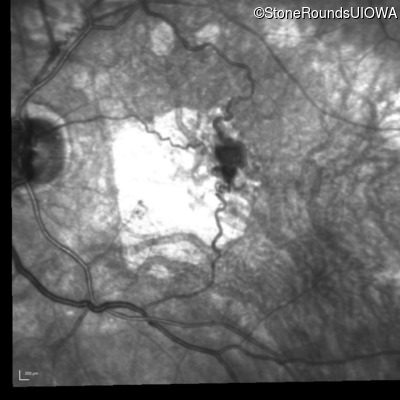

Fluorescein Angiography - Right - 20/125

Exemplar